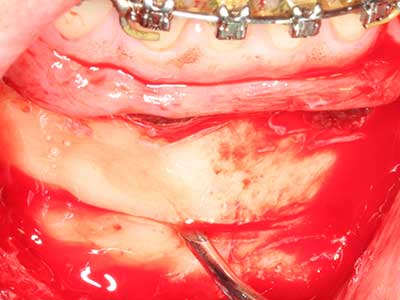

Fig. 18: preparazione di una copertura corticale con sega piezoelettrica per osso (Piezomed, W&H).

Fig. 19: sito chirurgico dopo neurolisi e rimozione dell'osteoma.

Fig. 20: la copertura ossea rimossa viene riadattata e fissata con una vite per osteosintesi (KLS Martin, Tuttlingen).